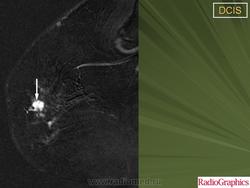

Обычно, ПКИС никак не проявляется и не выявляется при физикальном исследовании. Однако у небольшого числа женщин может отмечаться опухолевидное образование либо какие-то выделения из соска. Чаще всего протоковая карцинома выявляется на маммографии. Дело в том, что «старые» раковые клетки отмирая, не успевают полностью утилизироваться. В результате этого эта область пропитывается солями кальция (так называемое обызвествление) – образуются микрокальцинаты. Эти микрокальцинаты как раз и выявляются на маммограмме. В случае если полученные результаты маммографии врач считает подозрительными на рак, проводится следующий этап диагностики – биопсия.

Диагноз протокового рака - ПКИС не опасен для жизни женщины. Это неинвазивная форма рака и она представляет собой самую раннюю его стадию – стадию 0, которую иногда даже называют «предрак». Да, это рак, это неконтролируемый рост клеток, однако этот рост отмечается лишь в просвете молочных протоков и не выходит за их пределы. Хотя эта форма рака и является неинвазивной, всегда есть риск того, что в последующем она перерастет в инвазивный рак – то есть такой, который распространяется на нормальные ткани молочной железы. От 25 до 50% женщин, перенесших по поводу ПКИС хирургическое лечение (без лучевой терапии) имеют шанс в будущем «заработать» инвазивный рак молочной железы. В большинстве случаев эти рецидивы встречаются через 5 – 10 лет после выявления ПКИС.